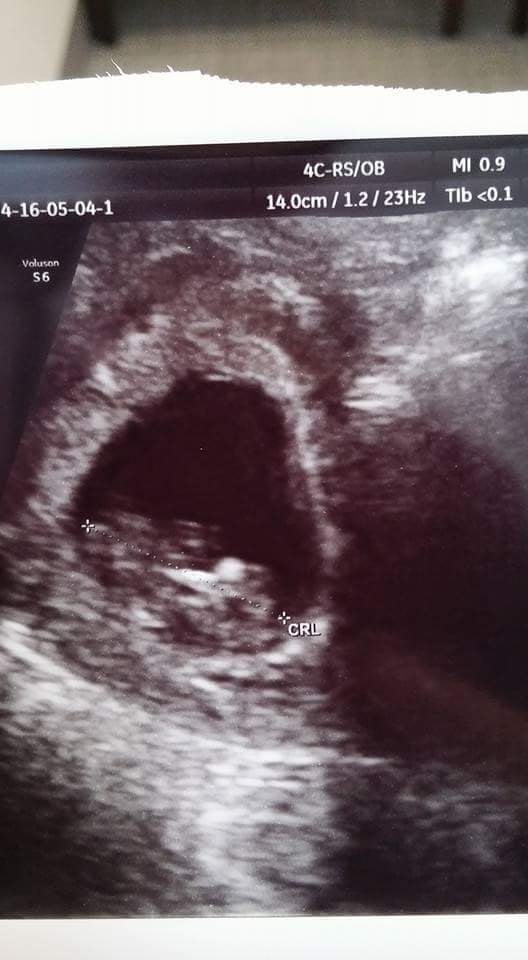

I had both levels of U/S - level II is a lot clearer and the machines are a LOT newer and have all these gadgets and buttons on them. There's definitely a difference in machines and picture quality. They're both 2D and black and white, but level II machines are a lot clearer/sharper and less fuzzier. Here's examples: Granted, these are 1st trimester ones but I don't have any pics in my phone from the 2nd trimester U/S.

Level II @ 9 weeks at RE's (where they use level II machines) and regular U/S @ OB at 10 weeks